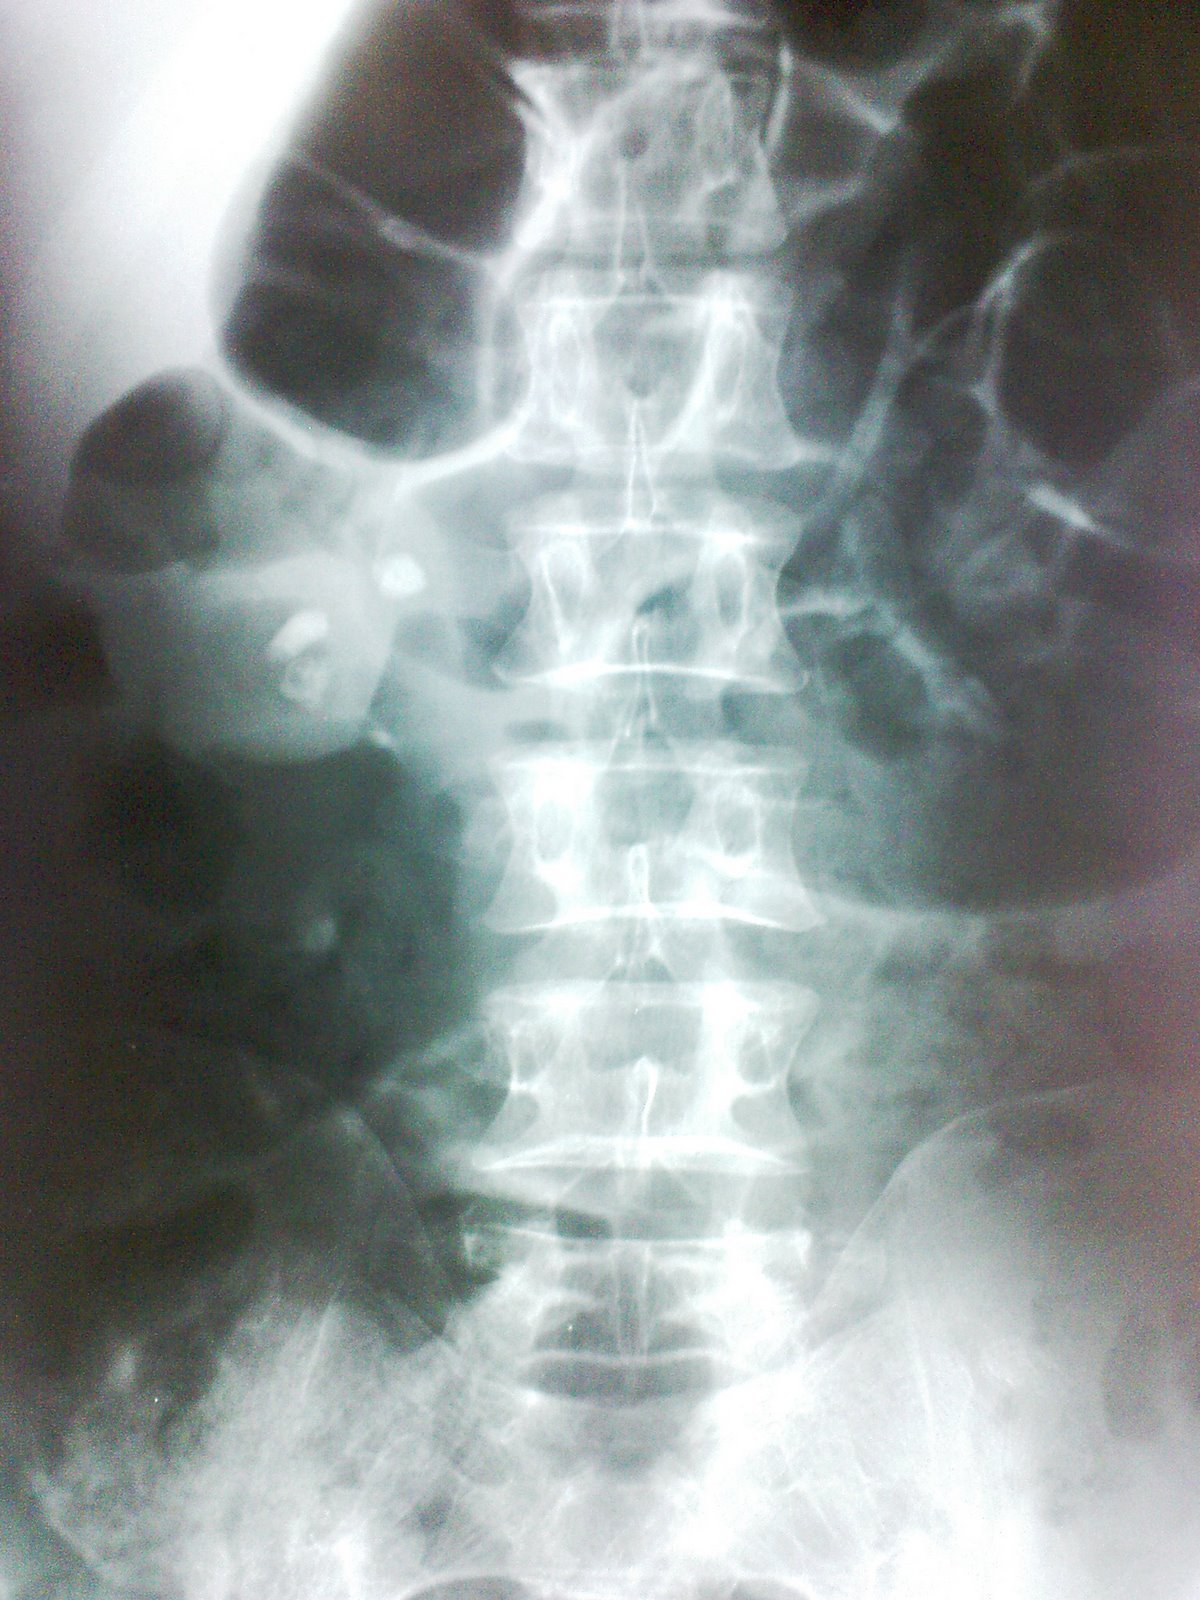

Sentinel Loop X Ray . — the sentinel loop sign is a radiographic finding of localized ileus on abdominal radiographs, indicating. A localized ileus, also called sentinel loops, is a functional type of obstruction caused by irritation of a loop or loops of bowel. — learn about the radiological features of sentinel loop, a localized loop of dilated small bowel caused by intra. — adynamic ileus is a paralysis of intestinal motility that can be caused by various conditions. [1] simply put, it is the. the sentinel loop sign refers to the appearance of localized ileus on abdominal radiographs, which indicates the presence. A sentinel loop is a radiographic finding of a. a sentinel loop is a sign seen on a radiograph that indicates localized ileus from nearby inflammation. — learn how to identify and diagnose closed loop obstruction in the small bowel on ct, a serious condition that can lead to bowel infarction. — learn how to identify and categorize abnormal bowel gas patterns on radiographs and ct scans.

A localized ileus, also called sentinel loops, is a functional type of obstruction caused by irritation of a loop or loops of bowel. — learn how to identify and diagnose closed loop obstruction in the small bowel on ct, a serious condition that can lead to bowel infarction. a sentinel loop is a sign seen on a radiograph that indicates localized ileus from nearby inflammation. the sentinel loop sign refers to the appearance of localized ileus on abdominal radiographs, which indicates the presence. — learn about the radiological features of sentinel loop, a localized loop of dilated small bowel caused by intra. — the sentinel loop sign is a radiographic finding of localized ileus on abdominal radiographs, indicating. A sentinel loop is a radiographic finding of a. — learn how to identify and categorize abnormal bowel gas patterns on radiographs and ct scans. — adynamic ileus is a paralysis of intestinal motility that can be caused by various conditions. [1] simply put, it is the.

Sentinel Loop Sign In Acute Pancreatitis In acute pancreatitis, the Sentinel Loop X Ray a sentinel loop is a sign seen on a radiograph that indicates localized ileus from nearby inflammation. A localized ileus, also called sentinel loops, is a functional type of obstruction caused by irritation of a loop or loops of bowel. [1] simply put, it is the. — learn how to identify and categorize abnormal bowel gas patterns on. Sentinel Loop X Ray.

A plain abdominal Xray (in decubitus) revealed a prominent sentinel Sentinel Loop X Ray A sentinel loop is a radiographic finding of a. [1] simply put, it is the. the sentinel loop sign refers to the appearance of localized ileus on abdominal radiographs, which indicates the presence. — adynamic ileus is a paralysis of intestinal motility that can be caused by various conditions. — learn how to identify and categorize abnormal. Sentinel Loop X Ray.

Sentinel loop sign and colon cutoff sign in a similar plain abdominal Sentinel Loop X Ray — learn about the radiological features of sentinel loop, a localized loop of dilated small bowel caused by intra. A localized ileus, also called sentinel loops, is a functional type of obstruction caused by irritation of a loop or loops of bowel. a sentinel loop is a sign seen on a radiograph that indicates localized ileus from nearby. Sentinel Loop X Ray.